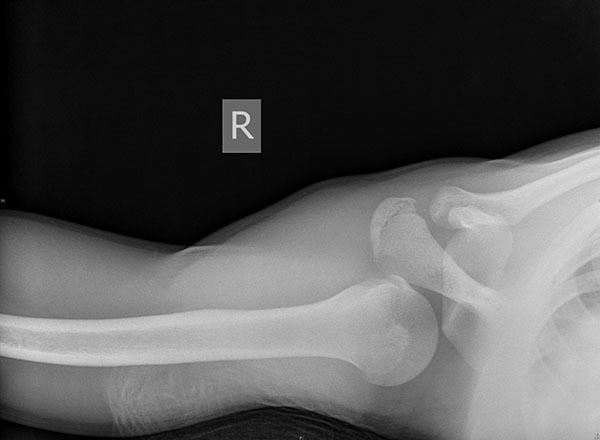

Physical examination in poster dislocations typically shows anterior shoulder flattening with a posterior prominence and an inability to rotate or abduct externally. The arm may be locked in an internally rotated position. Plain film imaging may appear normal or reveal a “lightbulb” appearance of the humeral head; however, the trans-scapular Y view should demonstrate a humeral head posterior to the glenoid fossa. (See Figures 3 and 4.) A Velpeau view may be obtained if the patient cannot comply with a trans-scapular Y.44

Figure 4. Posterior Dislocation Axillary View |

![]() |

Courtesy of J. Stephan Stapczynski, MD. |